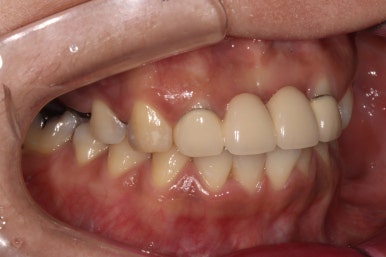

정면에서 보았을 땐, 기존에 제작되어있던 PFM 브릿지가 시간이 지나 그 경계가 조금 보이는 것 말곤 특별히 문제는 없어보였습니다. 아마도 앞니에 큰 문제가 없었기에 내원이 조금 늦어지신 것이 아닌가 싶었어요.

왼쪽위 처음 내원하셨을 당시, 오른쪽이 앞니 지르코니아 완성 후 정면 사진입니다.

아직 어금니는 완성되지 않았지만..!...

보시면 파란색 화살표로 표시된 두 측절치에 기존에 치료받으셨던 PFM 브릿지의 경계가 드러나 회색 라인이 생기신 것을 보실 수 있고, 잇몸이 올라가버려 비교적 비 심미적인 모습인 것을 확인하실 수 있습니다.

지르코니아 브릿지로 교체함으로써 예쁜 첫인상을 완성해드렸어요.

이렇게 치료 중간에 환자분과 상의하면서 치아 색상을 적절히 채득해놓기에 가능한 일입니다.

본 환자분 같은 경우에는 자연스러운 치아 색상을 원하셔서 따뜻한 느낌의 색상으로 완성하였는데, 경우에 따라 보다 밝은 색상으로의 변화도 가능합니다! 연예인 라미네이트처럼요.